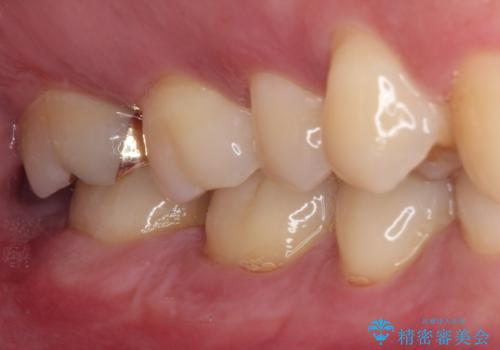

ゴールドインレーは銀歯のインレーやセラミックインレーと比べ、「技工操作の精度が高く、適合が著しく良い」というメリットがあります。特に上の奥歯は歯科医師の操作が行いにくいため、「適合の良さ」は再治療のリスクを防ぐ上でとても重要な要素となります。

上の奥歯は金属色が見えることもないため、審美的な問題は全くありません。